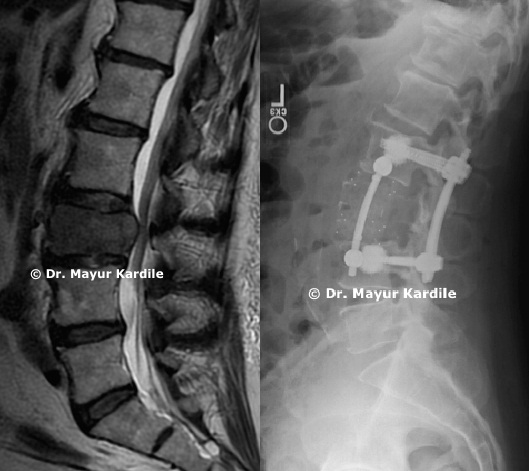

Recurrent disc hernaition with Formainal stenosis

67 yr lady